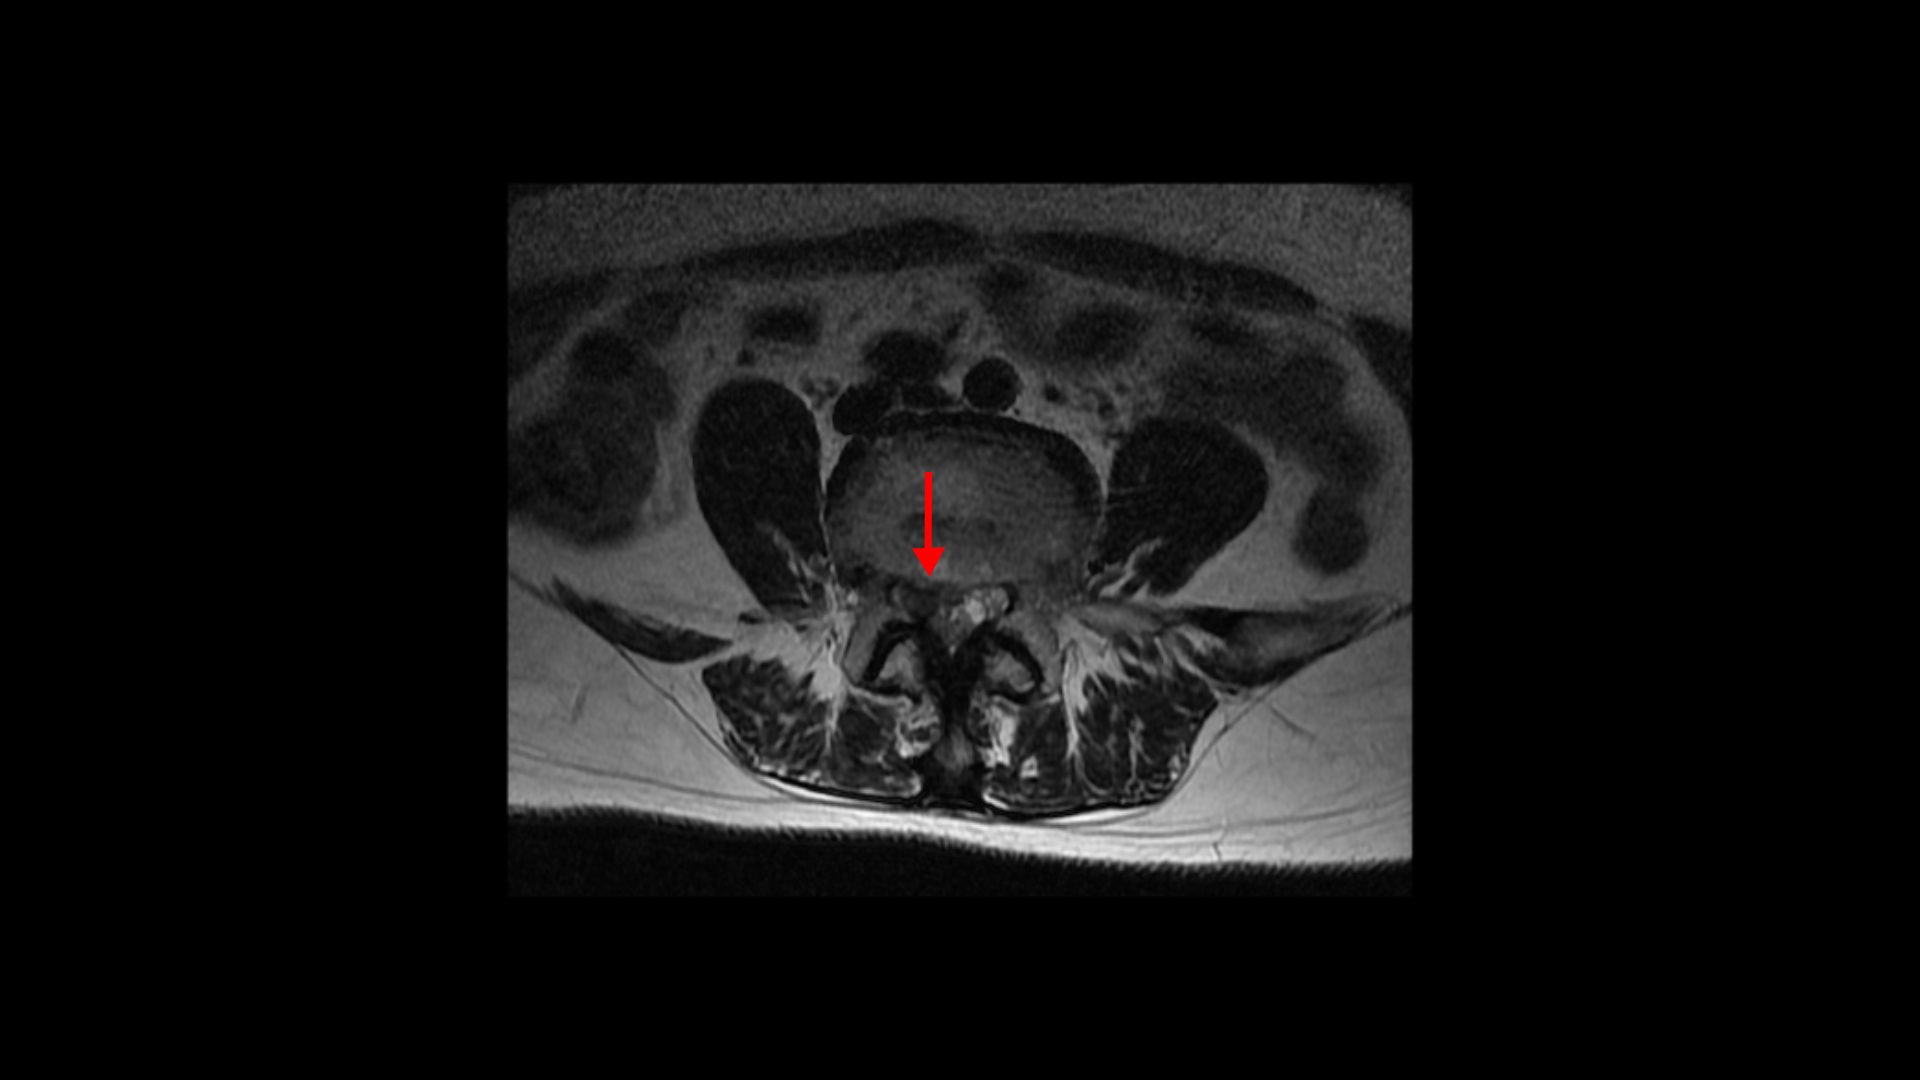

이분은 약 4달 전에 디스크가 갑자기 파열됩니다. MRI를 보면 4번 5번 디스크가 터져서 밀려나온 수핵이 아래로 흘러내려 있습니다.

축상면에서 보면 흘러내린 수핵이 신경이 있어야 할 자리를 차지하고 있는 것이 보입니다.

또 보시다시피 이 4번 5번 마디에서는 심한 중심성 협착도 있습니다.